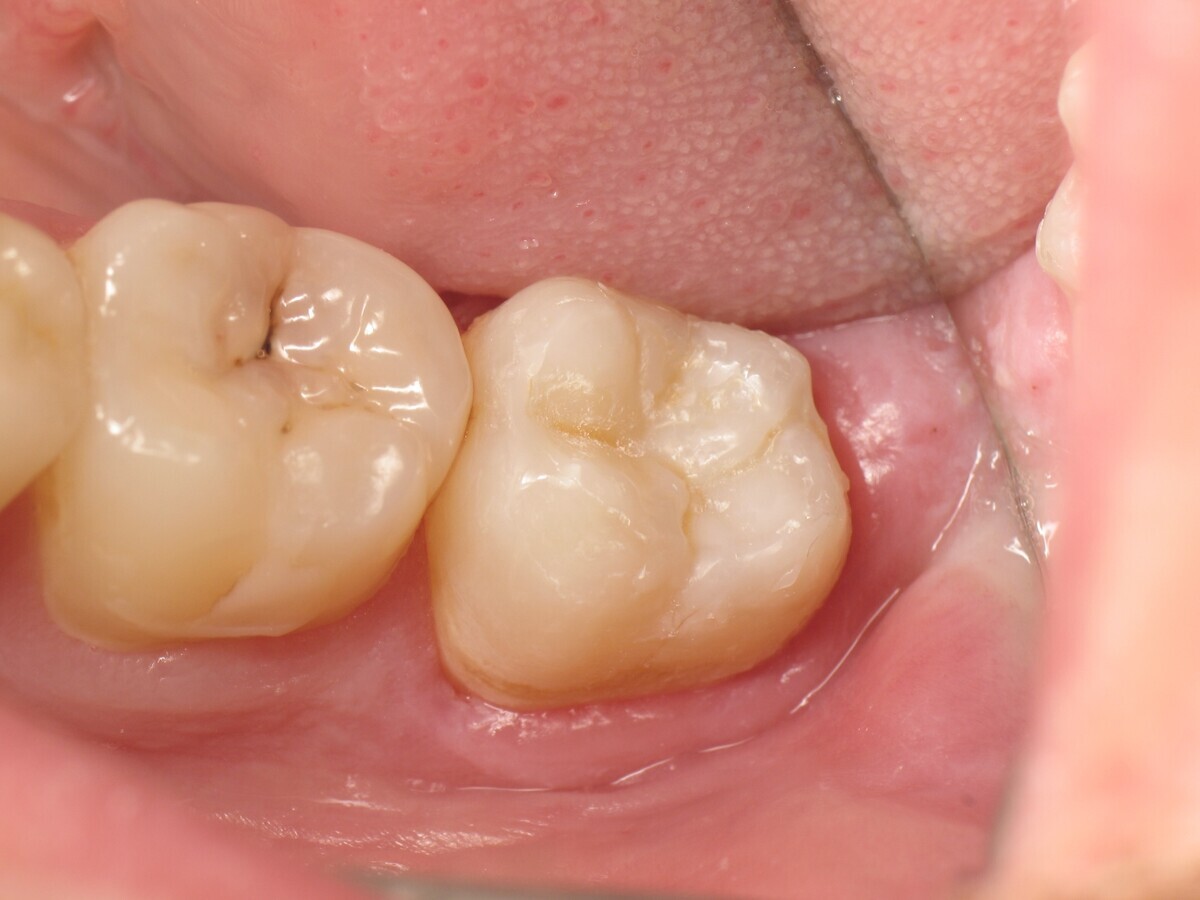

La secuencia fotográfica muestra la cavidad después de la aplicación y fotopolimerización del adhesivo y el modelado que se obtiene con el composite termoviscoso. Fotos: Yassine HARICHANE

El composite calentado tiene una consistencia fluida para un perfecto manejo y se puede aplicar en capas de hasta 4 mm (Figura 16). A medida que se enfría hasta la temperatura corporal, la viscosidad del composite termoviscoso aumenta, lo que lo hace muy fácil de modelar (Figura 17). Finalmente, se realiza la fotopolimerización durante 20 segundos (potencia ≥ 1.000 mW/cm2, Figura 18). El uso de un composite bulk permite un llenado rápido en un solo paso. Si se requiere una segunda capa, la capa superior también se puede realizar con composite termoviscoso estético universal VisCalor en color A1 (VisCalor, VOCO, Figura 19), que se fotopolimeriza en incrementos de 2 mm. La consistencia innovadora del composite termoviscoso permite una reproducción fácil de la anatomía y una eliminación fácil del exceso de material (Figura 20) [Ilie et al. 2014]. A continuación se aplica la almohadilla oclusal creada previamente (Figura 21). La fotopolimerización se realiza primero con la almohadilla y luego sin durante 20 segundos cada una (Figuras 22 a 24). No se requiere material separador entre el material compuesto y la almohadilla. Debido a la eliminación previa de la capa de inhibición de la almohadilla, hay muy pocos o ningún punto de contacto, de modo que no se puede crear ningún enlace químico real entre la almohadilla y la resina. Los pocos puntos de contacto presentes solo significan que puede sentir una ligera resistencia cuando se retira la almohadilla después del primer ciclo de fotopolimerización.

Figura 13. Fotopolimerización del adhesivo.

Figura 14. Fondo de la cavidad con GrandioSO Light Flow.

Figura 17. Modelado de VisCalor Bulk.